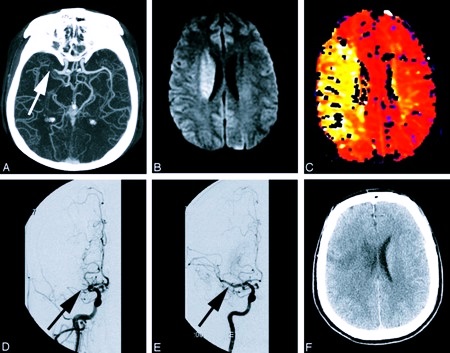

Выделяют три основных вида инсульта: ишемический, геморрагический и субарахноидальный (САК). Чаще разделяют на два типа: инфаркт и кровоизлияние в ткани мозга. Ишемическая форма встречается в пять раз чаще, чем геморрагическая.

Это самый распространенный вид инсульта. Диагностируется у 75% пациентов. Ишемия или инфаркт мозга, что одно и то же, обозначает участок, к которому перестала поступать кровь, а с ней и необходимый кислород. Без питания ткань мозга через три часа отмирает. Из-за некроза нейронные клетки погибают, вернуть их к прежнему состоянию невозможно. Мертвое уже не восстанавливается. Поэтому инсультники редко достигают полного выздоровления.

Причина инсульта головного мозга – закупорка или сужение просвета сосудов. В зависимости от места, где образовался тромбоз, характера повреждения, зависит физическое состояние больного и успешность лечения. Реологическое состояние крови и патология магистральных артерий со временем приводит к ишемии и некрозу участков, оставшихся без кислорода.

Человек может впасть в кому, при этом глазные яблоки продолжают двигательную активность. По внешним проявлениям можно прийти к выводу, что область поражения – мозговой ствол. Точный диагноз подтверждается с помощью КТ или МРТ.

Как происходит субарахноидальный инсульт головного мозга? При кровоизлиянии кровь попадает под паутинную оболочку и заполняет базальные цистерны, борозды полушарий. ОНМК бывает очаговым либо общемозговым, охватывающим все пространство. Происходит спазм сосудов, который нарастает постепенно. Больным на 3–4 сутки становиться хуже.

Это спазмолитическое последствие кровоизлияния, пик которого наступает через неделю или две. Если не сделать срочную операцию, при обширном инфаркте мозга человек погибает. У 20–25% пациентов кровоизлияние повторяется, после этого в 70% случаев смерть неизбежна.